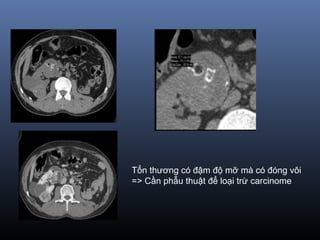

Tổn thương có đậm độ mỡ mà có đóng vôi

=> Cần phẫu thuật để loại trừ carcinome